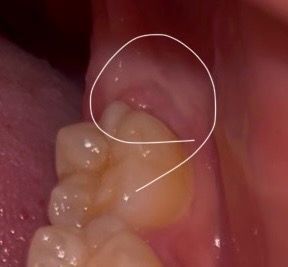

어금니 뒤 통증이 있어서 보니까 뭔가 튀어나와있어요

왼쪽 어금니 뒤에가 아파서 보니 뭔가 부어있는듯한게 있는데 단순염증인가요? 아니면 사랑니가 나오고 있는건가요? 왼쪽에 사랑니가 있다고 듣긴 했습니다.

진통소염제 애드빌 먹고있는데 그래도 아프면 치과에 가야할까요? 참고로 경구피임약 복용중입니다.

사진에 보이는 부분은 사랑니가 매복되어 잇는 거 같습니다. 사랑니 떄문에 잇몸이 약간 튀어 나온거 같습니다.

잇몸은 호르몬상태에 따라 영향을 받기도 하고 전신건강의 영향을 받기도 합니다 꼭 사랑니때문에 생긴 치관주위염이 아닐 수도 있습니다